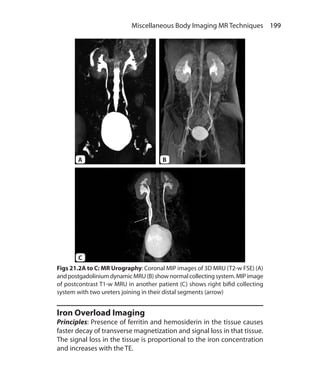

MR Urography	 198

Iron Overload Imaging	 199

Magnetic Resonance Elastography	 201